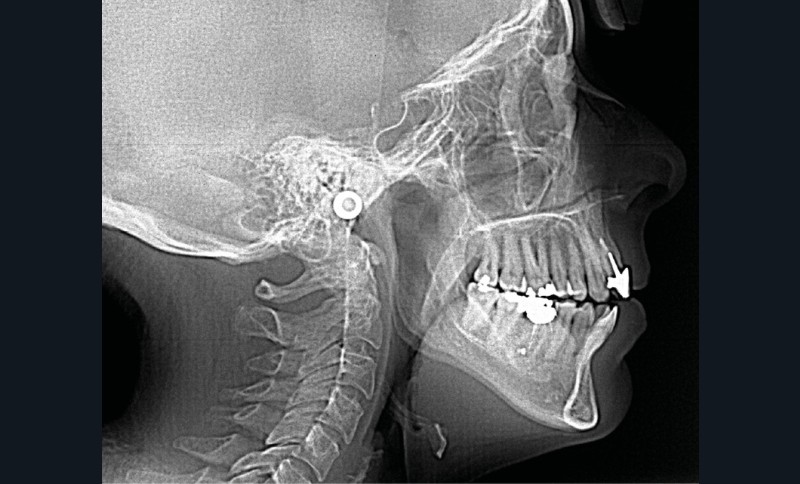

L’analyse endobuccale et l’étude céphalométrique (fig. 2, tableau 1) confirment le diagnostic de classe II squelettique hyperdivergente avec une classe II molaire et canine bilatérale, associée à un encombrement, à une dysharmonie du sens transversal par endoalvéolie maxillaire, et une béance antérieure par infra-alvéolie incisive maxillaire dans un contexte dysfonctionnel de la musculature péri-labiale et mentonnière.

Tableau 1 : Valeurs céphalométriques |

|||

Valeur moyenne |

Avant traitement – 10/04/2008 |

Après contention – 19/12/2011 |